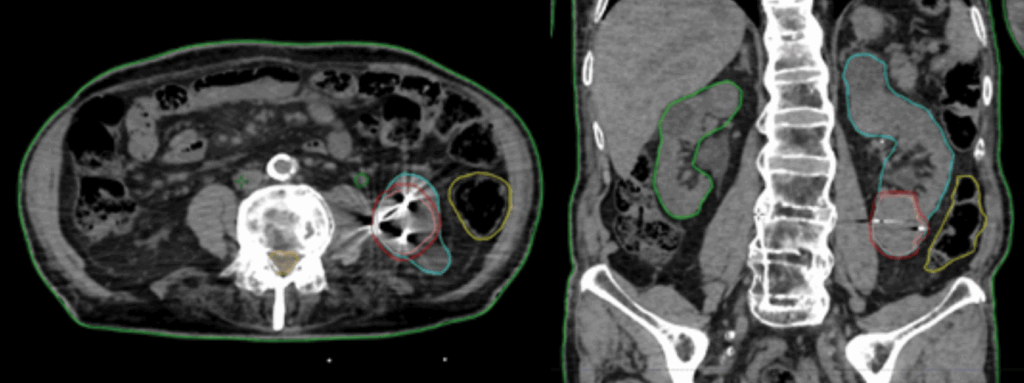

Prescription40 Gy in 5 consecutive fractions over one week (figure 2)

Figure 2: Axial and coronal views from the patient’s SBRT plan illustrating the radiation dose distribution.